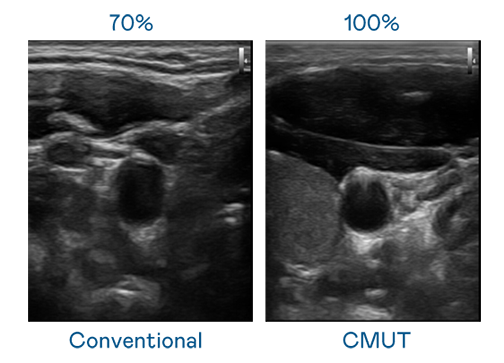

CMUT 技术是一种用电容式微机电元件来产生超音波讯号的技术。与传统 PZT 压电式技术相比,CMUT 频宽增加 30%,更宽频的超音波讯号让影像解析度大幅提升,是实现高影像品质医疗超音波扫描、促进精准医疗发展的关键技术。

超音波影像的解析度高低,首先取决于探头能发出的讯号频宽。创世红海 CMUT 可提供高清晰的超音波讯号,提供高频宽、高灵敏度、影像纹理细节更高的超音波影像,协助医护人员缩短影像判读时间及利用精准的医疗影像进行诊断。